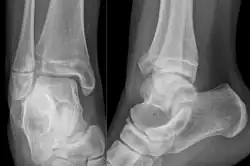

-

A triplane fracture of the ankle as seen on plain X-ray